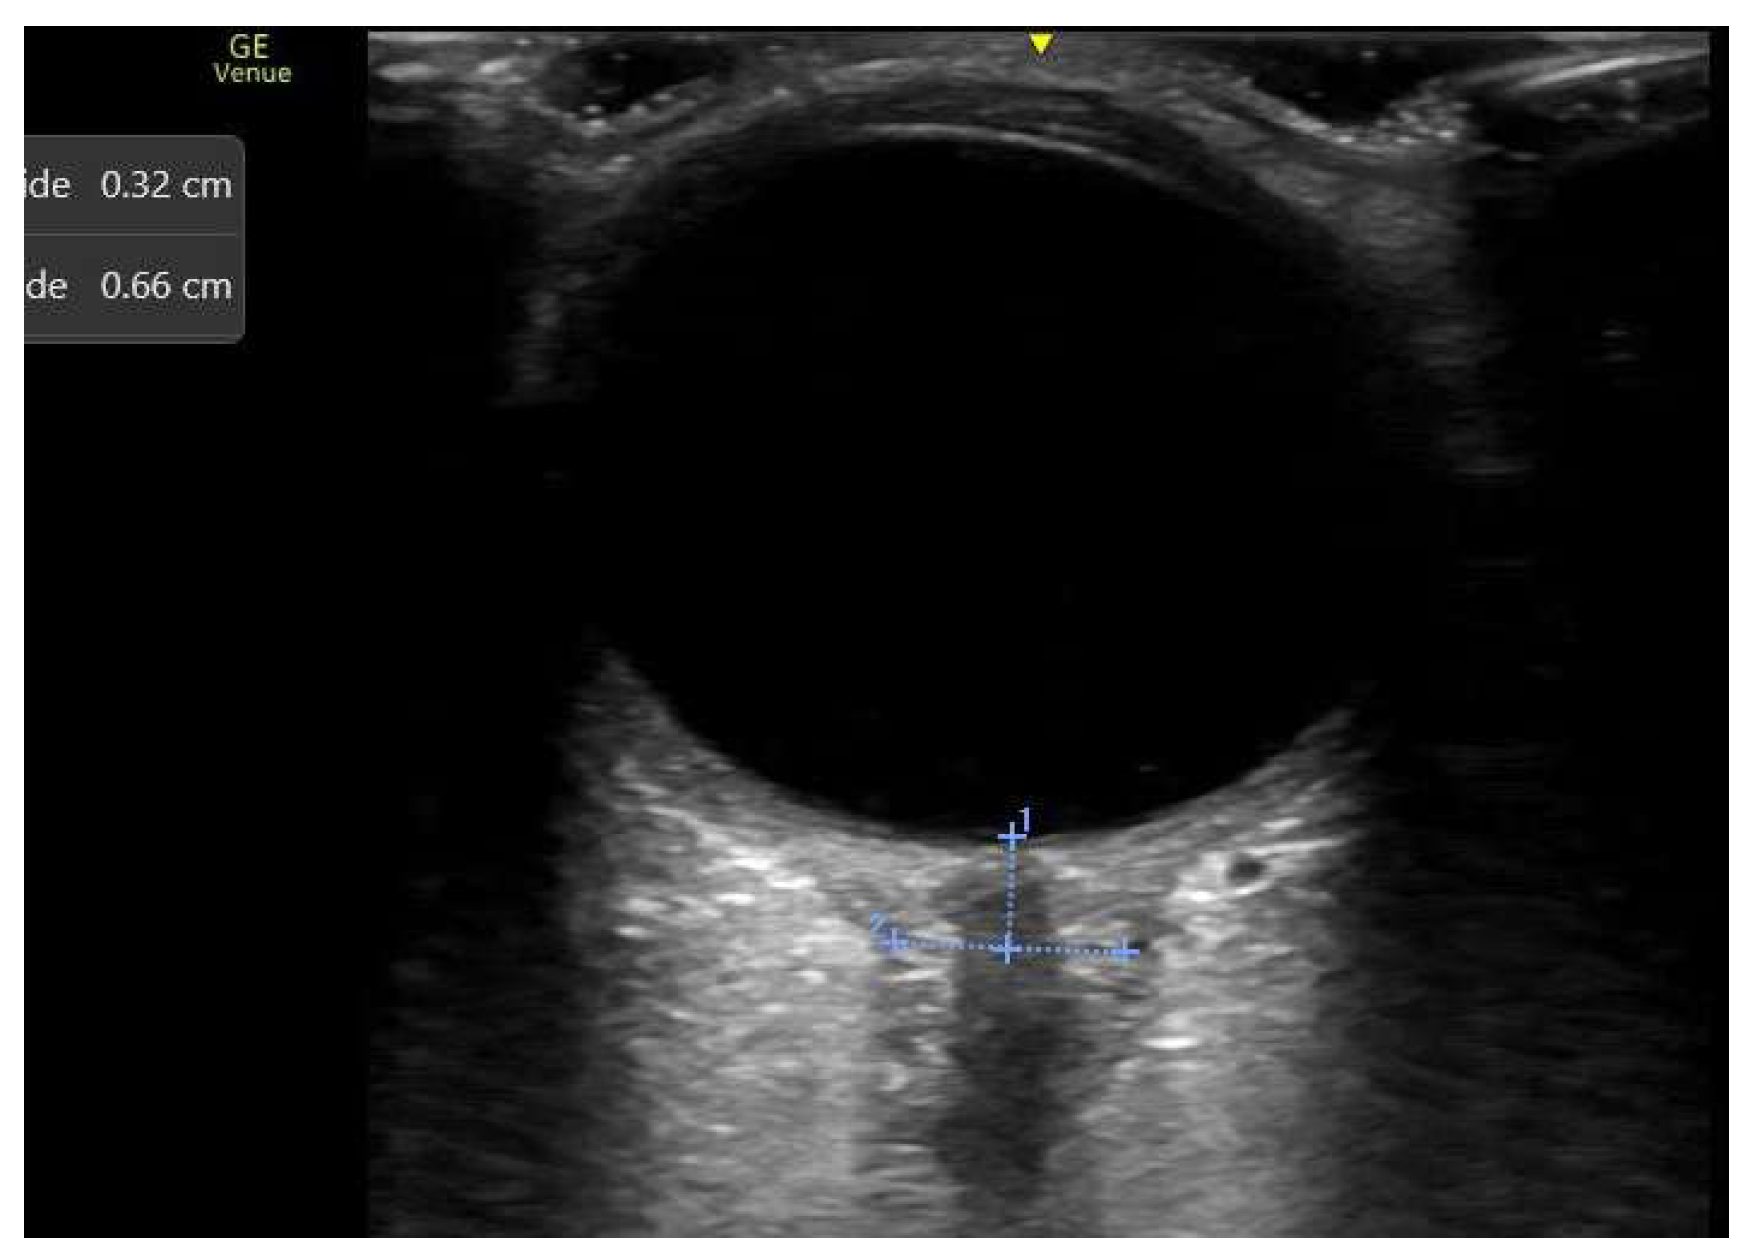

3.1.5. Centrally Inserted Central Catheters (CICC)

- Venous TCCD, combined with IJV ultrasound, offers real-time, early detection of cerebral venous outflow impairment, allowing timely and targeted adjustments to prevent secondary IH in critically ill and surgical patients.